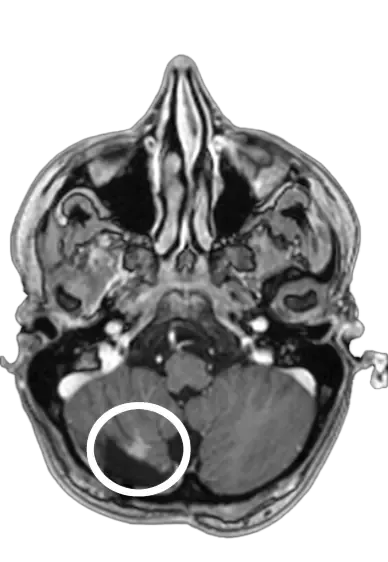

SmartContrast uses AI to reduce gadolinium contrast agent usage while maintaining full diagnostic image quality. Use just 1/3rd of the standard dose and let AI enhance the output to match full-dose quality.

Full diagnostic qualityAdvanced deep learning algorithms enhance low-dose images to match the diagnostic quality of full-dose scans.